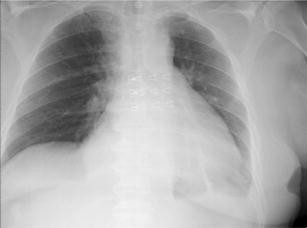

Chest X-ray revealing enlarged heart, but neither pleural nor parenchymal abnormalities